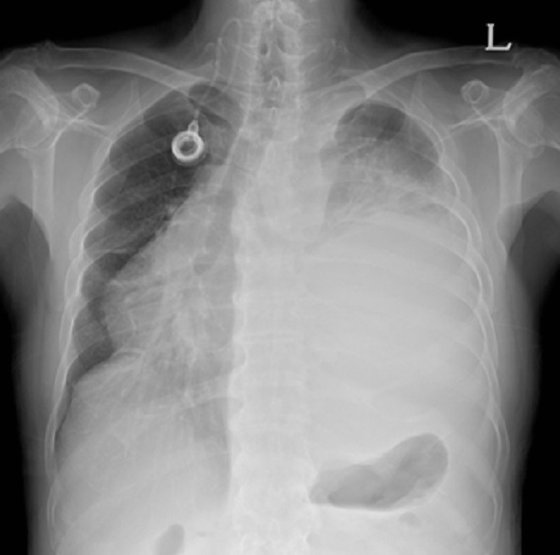

폐암 초기증상 - 3. 객혈

우선 객혈은 기침할 때 배출되는 가래에 혈액이 섞여 나오는 것을 말합니다. 암세포가 작더라도 기관지를 뚫고 들어가면 혈관이 발달하여 이 부분을 자극하게 되고, 기침이나 가래를 뱉을 때 객혈이 나타날 수 있습니다. 뚜렷한 이유 없이 피를 토한다면 폐암일 수 있습니다.